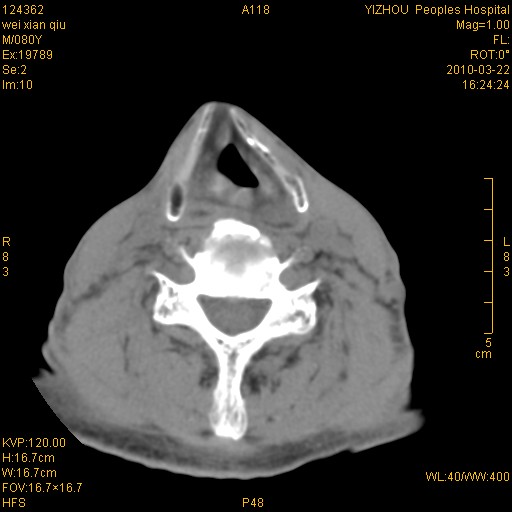

男,80岁.声嘶三月余.

喉前庭右侧壁明显增厚,并见向内突出的软组织密度新生物,表面光滑,其后方软组织层次尚清晰,多考虑:喉部乳头状瘤!建议喉镜并病检!